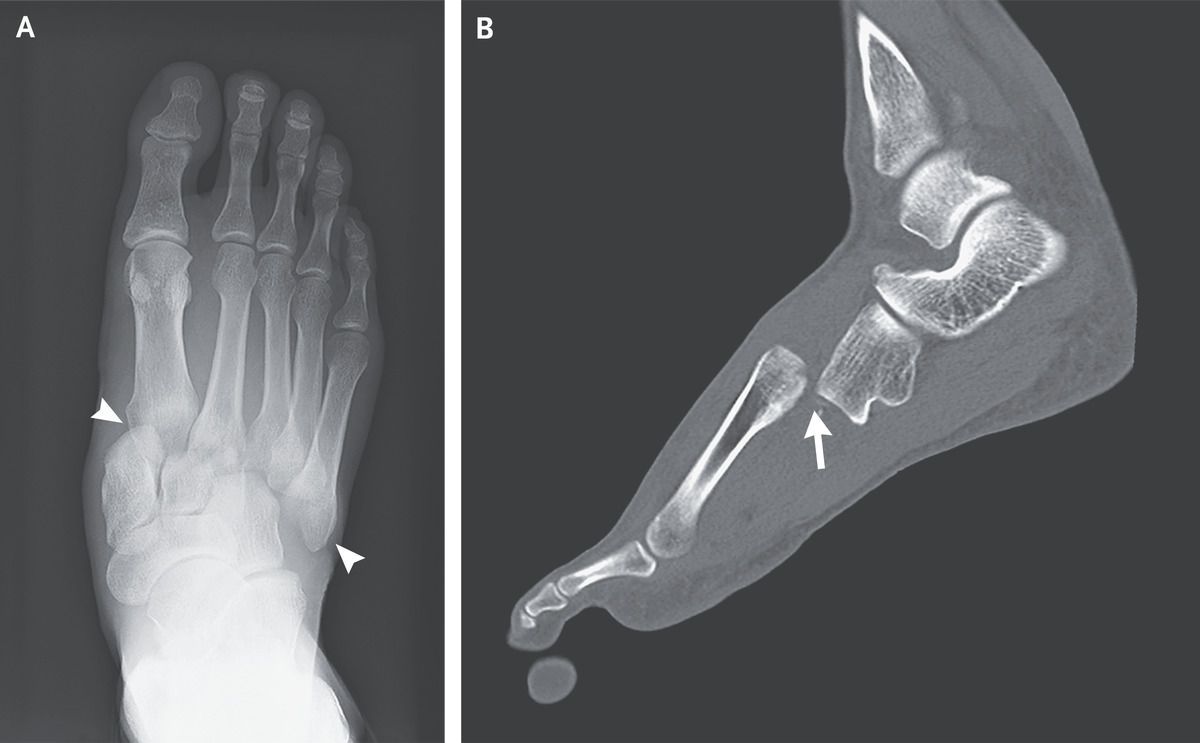

A 34-year-old man presented to the emergency department with sudden onset of pain in his right foot after landing a jump during a handball game. On physical examination, there was swelling and bruising on the dorsum of the right foot, and the patient was unable to bear weight on the foot. Non–weight-bearing radiographs showed lateral displacement of the first through fifth metatarsal bones from the cuneiform bones and the cuboid (Panel A, arrowheads). Computed tomography of the right foot revealed lateral and dorsal dislocation of the first through fifth metatarsal bones from the cuneiforms and cuboid (Panel B, arrow), as well as fractures of the first and second proximal metatarsals. The patient received a diagnosis of Lisfranc injury — an injury to the tarsometatarsal joint complex that can range in severity from soft-tissue damage to fractures with displacement. Lisfranc injuries are rare and may be misdiagnosed owing to subtle findings on radiography or to the presence of other, distracting injuries. The presence of substantial foot pain after even minor trauma should arouse suspicion for this condition. The patient underwent immediate surgical repair without complications. At follow-up 10 weeks after surgery, he could fully bear weight on the foot, and at follow-up 6 months later, his gait was normal.